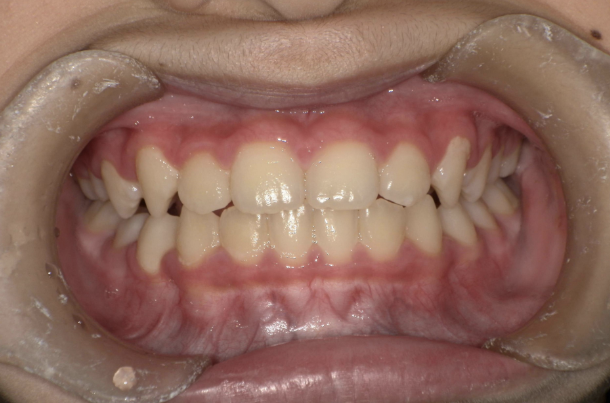

10歳を過ぎてからの矯正治療の場合、大人の歯を抜いて治療することが多くなります。 一方、下の前歯が生えてくる5〜7歳頃から治療を始めると、大人の歯を抜かずに治療することが可能です。 抜かずに治療するには早期に治療を開始することが大切です。

矯正治療でよく使われるはり金の装置は目立ってしまいます。 当院では、こども専用の取り外し式のマウスピース型装置を用います。 装置を使うのはご自宅で起きている時の1時間と夜寝ている時です。 学校につけていく必要が無いので、周りの人に気づかれずに治療を進められます。

取り外し式のマウスピース型装置はシリコン製で柔らかいです。 痛みを感じることはほとんどありません。

歯並びが悪いのは、あごの骨が成長不足で小さいことで起こります。 当院で行なっているこどもの歯ならび治療はあごの骨に働きかけることができます。 骨に働きかけることで成長不足のお子さんの骨が成長して、顔つきが良い方向に変わっていく可能性があります。 実は大きくなってからの矯正治療は歯が並んでいるだけで骨やお顔つきは変わっていないのです。 5〜7歳ぐらいで治療を開始すると成長不足の骨に働きかけて、より良い顔つきになれる可能性があります。